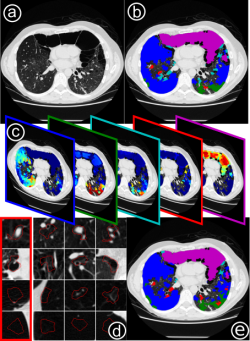

Weakly-supervised learning for mapping visual features to semantic profiles To learn models that capture the relationship between semantic clinical information and image elements at scale, we have to rely on data generated during clinical routine (images and radiology reports), since expert annotation is prohibitively costly. Here, we show that re-mapping visual features extracted from medical imaging data based on weak labels that can be found in corresponding radiology reports creates descriptions of local image content that captures clinically relevant information. In medical imaging (a) only a small part of the information captured by visual features relates to relevant clinical information such as diseased tissue types (b). However, this information is typically only available as sets of reported observations on the image level. Here, we demonstrate how to link visual features to semantic labels (c), in order to improve retrieval (d) and map these labels back to image regions (e). (Hofmanninger and Langs, 2015)